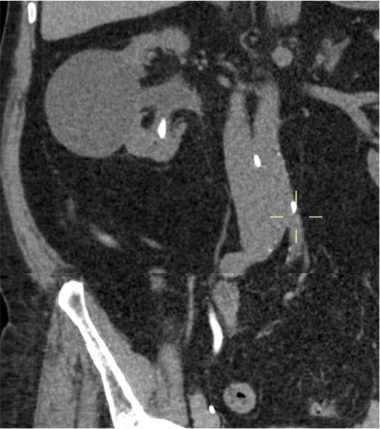

- Líquido en sistema colector de alta atenuación: puede ser dificil distinguir una simple hidronefrosis de una pionefrosis basándonos eclucisvamente en la atenuación del líquido.

- Estratificación del contraste en fase excretora.